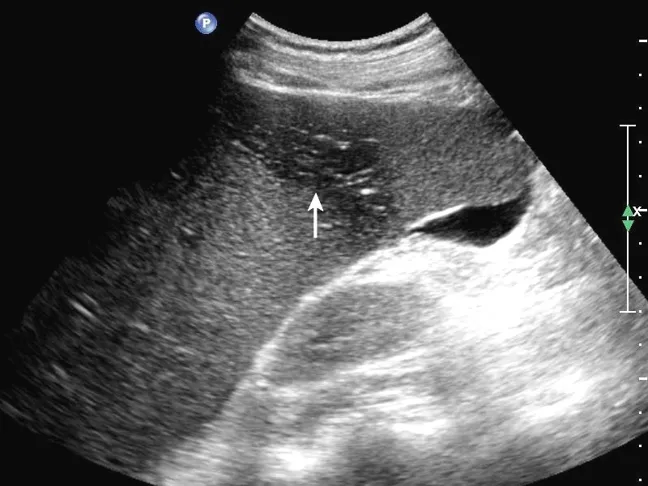

灰阶超声,副脾,显示脾门处一圆形回声与脾回声类似的副脾(箭头所示)

SP:脾脏